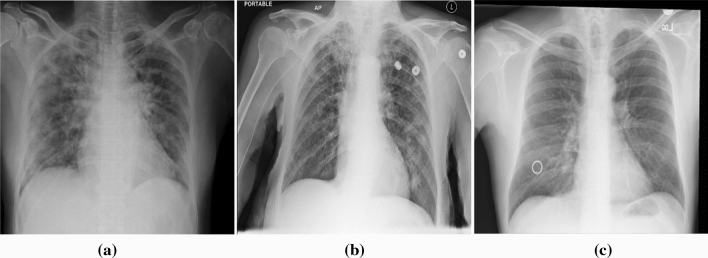

The data set used in this study was attained from the X-ray images used by Ozturk et al. [9] in their study. They have published this data set as an open resource at https://github.com/muhammedtalo/COVID-19. The data set consists of 125 COVID-19, 500 pneumonia, and 500 no-findings X-ray images. They used two different resources in the formation of the data set: COVID-19 X-ray images from the database attained from various open access resources by Cohen [41] and the ChestX-ray8 database provided by Wang et al. [42] for normal and pneumonia X-ray images. Forty-three of the patients in the COVID-19 data set are women and 82 are men. Metadata information for this data set are not provided for all patients. The average age of the 26 COVID-19 positive patients is approximately 55 years. It is a data set convenient for both binary and multi-class classifications. Figure 1 shows the X-ray images of some cases with COVID-19, pneumonia, and no-findings taken from the data set.

Fig. 1.

Sample X-ray images in the data set: a COVID-19, b Pneumonia, c No-Findings